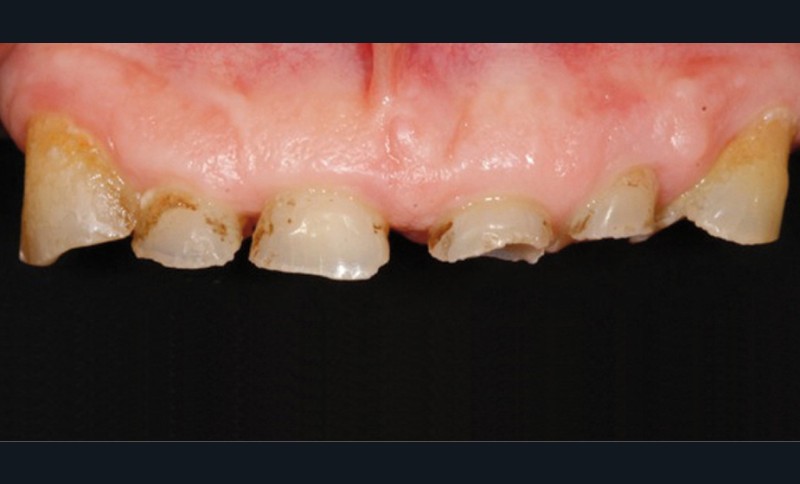

• L’examen intrabuccal montre de nombreux édentements non compensés (14, 15, 16, 24, 25, 26, 27, 47 et 36) ainsi que des pertes de substance très importantes, notamment dans le secteur antérieur.

– perte de substance extrême du bloc incisivo-canin maxillaire et des incisives mandibulaires ;